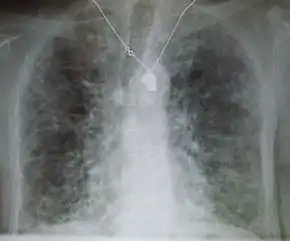

Pneumocystis pneumonia can present with interstitial lung disease, as seen in the reticular markings on this AP chest x-ray.